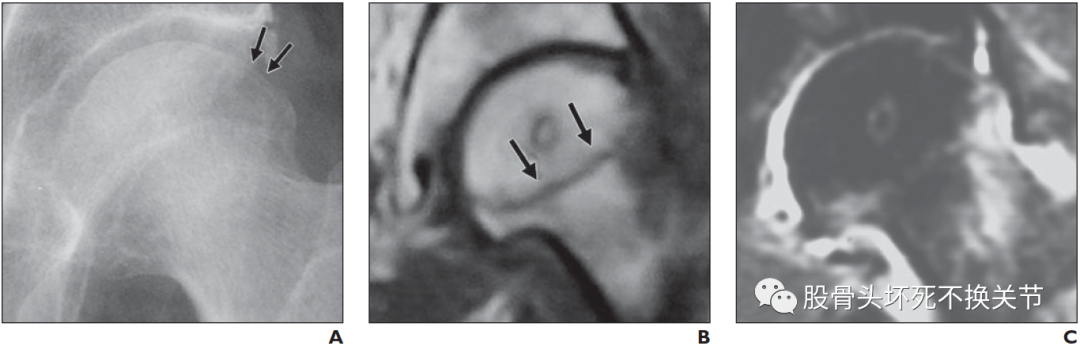

图a. 右股骨头蛙位X线片:股骨头前外侧软骨下高透明区(箭头)。图b. 股骨头冠状切面X线照片显示软骨下骨折(箭头所示),表现为新月征。注意:软骨下松质骨小梁的碎裂和压实,削弱了关节表面。肱骨头坏死的新月征:

A. 左髋关节前后位X线照片(Singh骨质疏松严重程度指数,V级),疼痛开始时显示新月征和股骨头上外侧塌陷(箭头所示)。

B. 冠状T1加权像显示股骨颈外侧部和转子间区弥漫性低信号强度。T1加权图像上的低强度带向关节面凹陷(箭头所示)。

C. 脂肪饱和质子密度像显示相应的高信号。